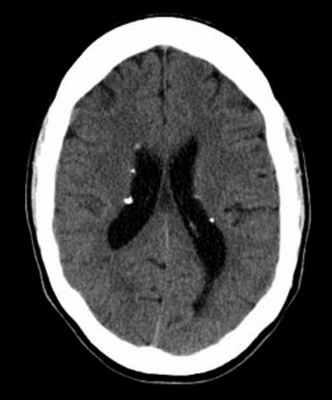

Наиболее типичными нарушениями в головном мозге являются корковые туберсы и субэпендимарные узлы. Туберсы могут быть как единичными, так и множественными, располагаются в виде выступов над единичной или прилегающими бороздами коры, расширяя их. Субэпендимарные узлы локализуются в стенках боковых желудочков и, реже, в стенках III и IV желудочков мозга. У новорожденных субэпендимарные узлы редко бывают кальцифицированными. По мере роста ребенка наблюдается постепенное отложение кальция в субэпендимарных узлах.

Субэпендимарные узлы в 10% случаев трансформируются в гиганто-клеточную астроцитому, которые манифестируют обычно между 5 и 10 годами жизни, имеют тенденцию к росту и локализуются у отверстия Монро

Субэпендимарные кальцификаты и корковые туберсы на КТ головного мозга ребенка с туберозным склерозом

Диагностировать туберозный склероз возможно лишь совместными усилиями нескольких специалистов (невролога, офтальмолога, дерматолога, кардиолога, нефролога) с проведением широкого аппаратного обследования пациента. Церебральная эпилептическая активность регистрируется при помощи ЭЭГ и ЭЭГ с пробами. У детей до года возможно проведение нейросонографии. Наибольшую значимость в диагностике поражений ЦНС имеют КТ и МРТ. КТ головного мозга более информативно в отношении кальцифицированных туберов и субэпендимальных узлов, а МРТ головного мозга — в выявлении некальцифицированных туберов. С целью своевременной диагностики астроцитомы детям, имеющим туберозный склероз, рекомендовано прохождение МРТ или КТ-исследования не реже чем раз в 2 года.

КТ головного мозга при туберозном склерозе. Видны кальцинированные субэпендимальные узелки в стенках боковых желудочков.